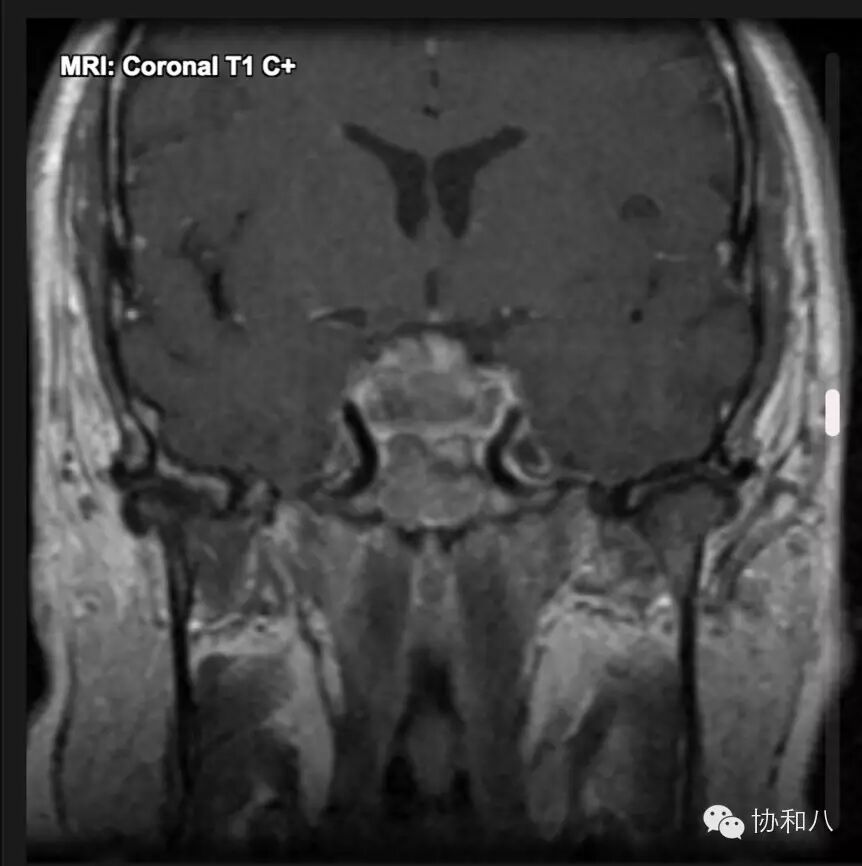

D. 增强冠状位T1WI

可见鞍区占位,T1 C+信号混杂,增强不均匀,符合出血坏死表现。